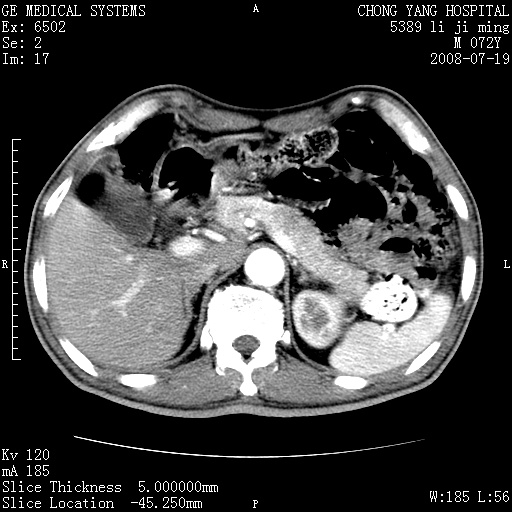

以下是引用zjzjr在2008-7-19 20:57:00的发言:[br]胰头增大,边缘模糊,周围可见渗出影,右侧肾前筋膜增厚.支持胰腺炎.

以下是引用yangyudong333在2008-7-20 6:56:00的发言:[br]胰腺增大尤以胰头明显,边缘模糊,周围可见渗出影,右侧肾前筋膜增厚,肠管於涨.支持胰腺炎

以下是引用不学无术在2008-7-19 23:15:00的发言:[br]胰腺增大尤以胰头明显,边缘模糊,周围可见渗出影,右侧肾前筋膜增厚,肠管於涨.支持胰腺炎